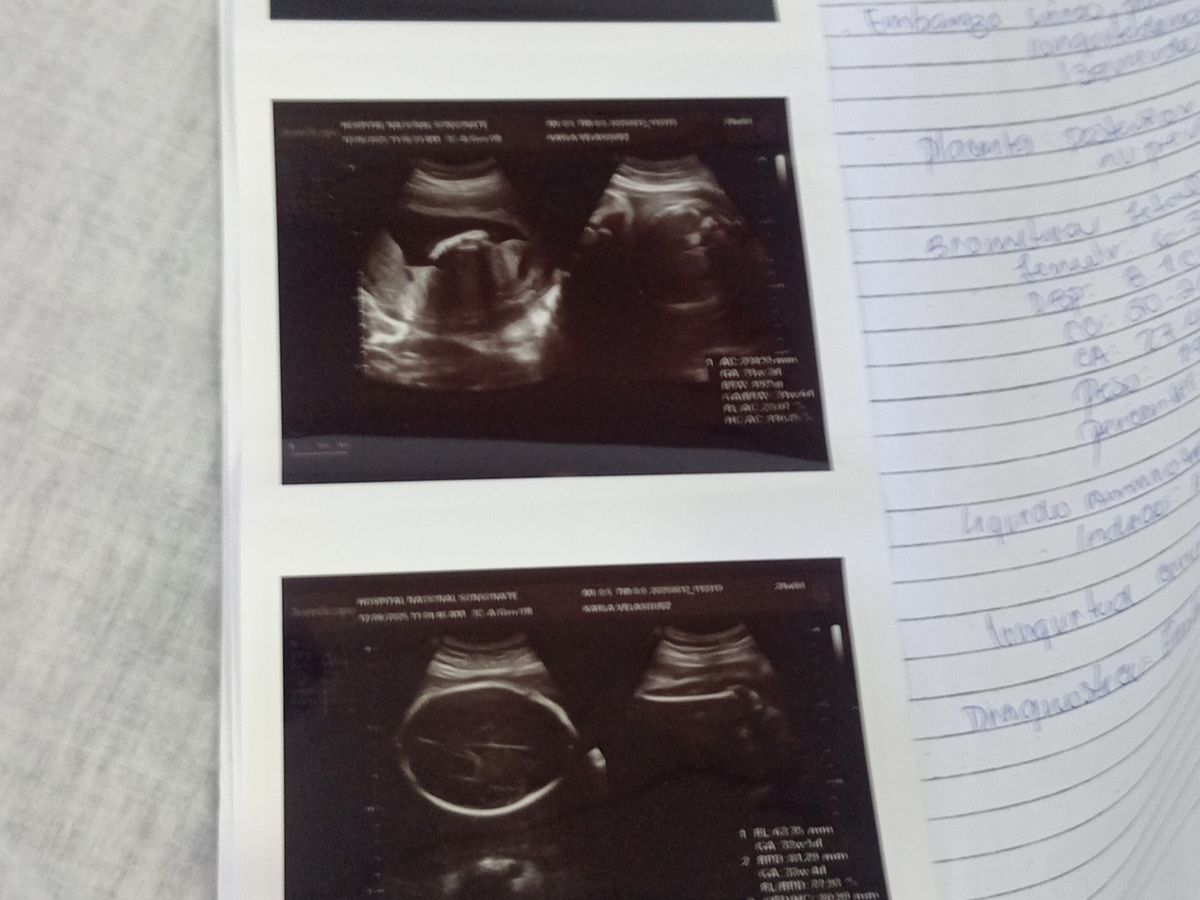

Me llamo Daniel y estoy recaudando para sacar a mi familia a delante, soy de escasos recursos y viene un hijo en camino